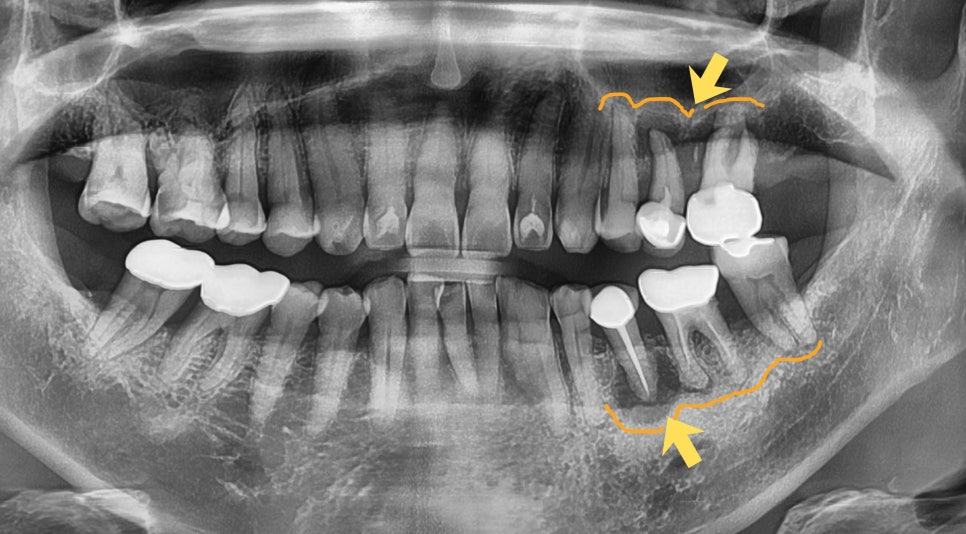

23.04.25 (치료전)- 24.09.04 (치료후)

3D CT를 통해 신경 위치, 뼈의 두께와 밀도, 상악동과의 거리까지 종합 분석한 뒤, 어느 각도로 얼마나 깊이 심을지 미리 설계하고 진행합니다. 특히 뼈이식과 상악동 거상술이 필요한 복잡한 케이스일수록 이 설계 과정이 더욱 중요합니다.